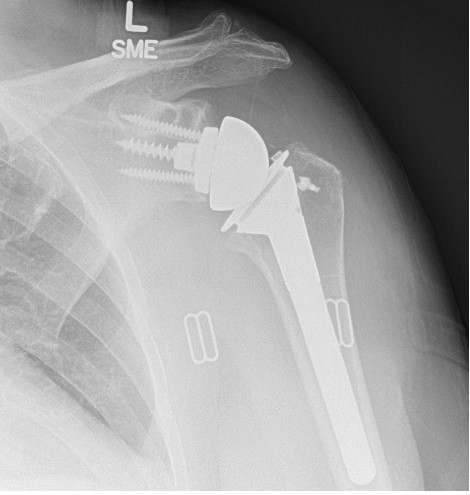

Pre-operative and post-operative xrays of a patient with rotator cuff tear arthropathy, treated with reverse total shoulder.

The reverse total shoulder was developed to help patients who have rotator cuff tears and shoulder arthritis. With a damaged rotator cuff, conventional anatomic total shoulder arthroplasty implants wear out too quickly. A reverse total shoulder involves replacing the ball and socket joints; however, the ball is moved to the "socket" side, and the "socket" is placed on the ball or humeral head side. This medializes and distalizes the center of rotation, allowing the deltoid muscle to raise the arm.

Although initially the reverse total shoulder was used for patients with shoulder arthritis with rotator cuff tears, it can also be used successfully in patients with shoulder arthritis who have significant glenoid or "socket" bone loss, complex proximal humerus fractures, chronic dislocations, revision of anatomic total shoulders, massive irreparable rotator cuff tears, and patients at high risk of developing rotator cuff tears with arthritis (advanced age, rheumatoid arthritis, etc.).

The reverse shoulder replacement uses a ball-and-socket joint where the ball is placed on the shoulder blade and the socket is placed on the top of the arm bone. This is reverse of our normal anatomy and is designed to make the deltoid muscle, the large shoulder muscle that caps the end of the shoulder, work better to make up for the deficiency of your worn out rotator cuff tendon.